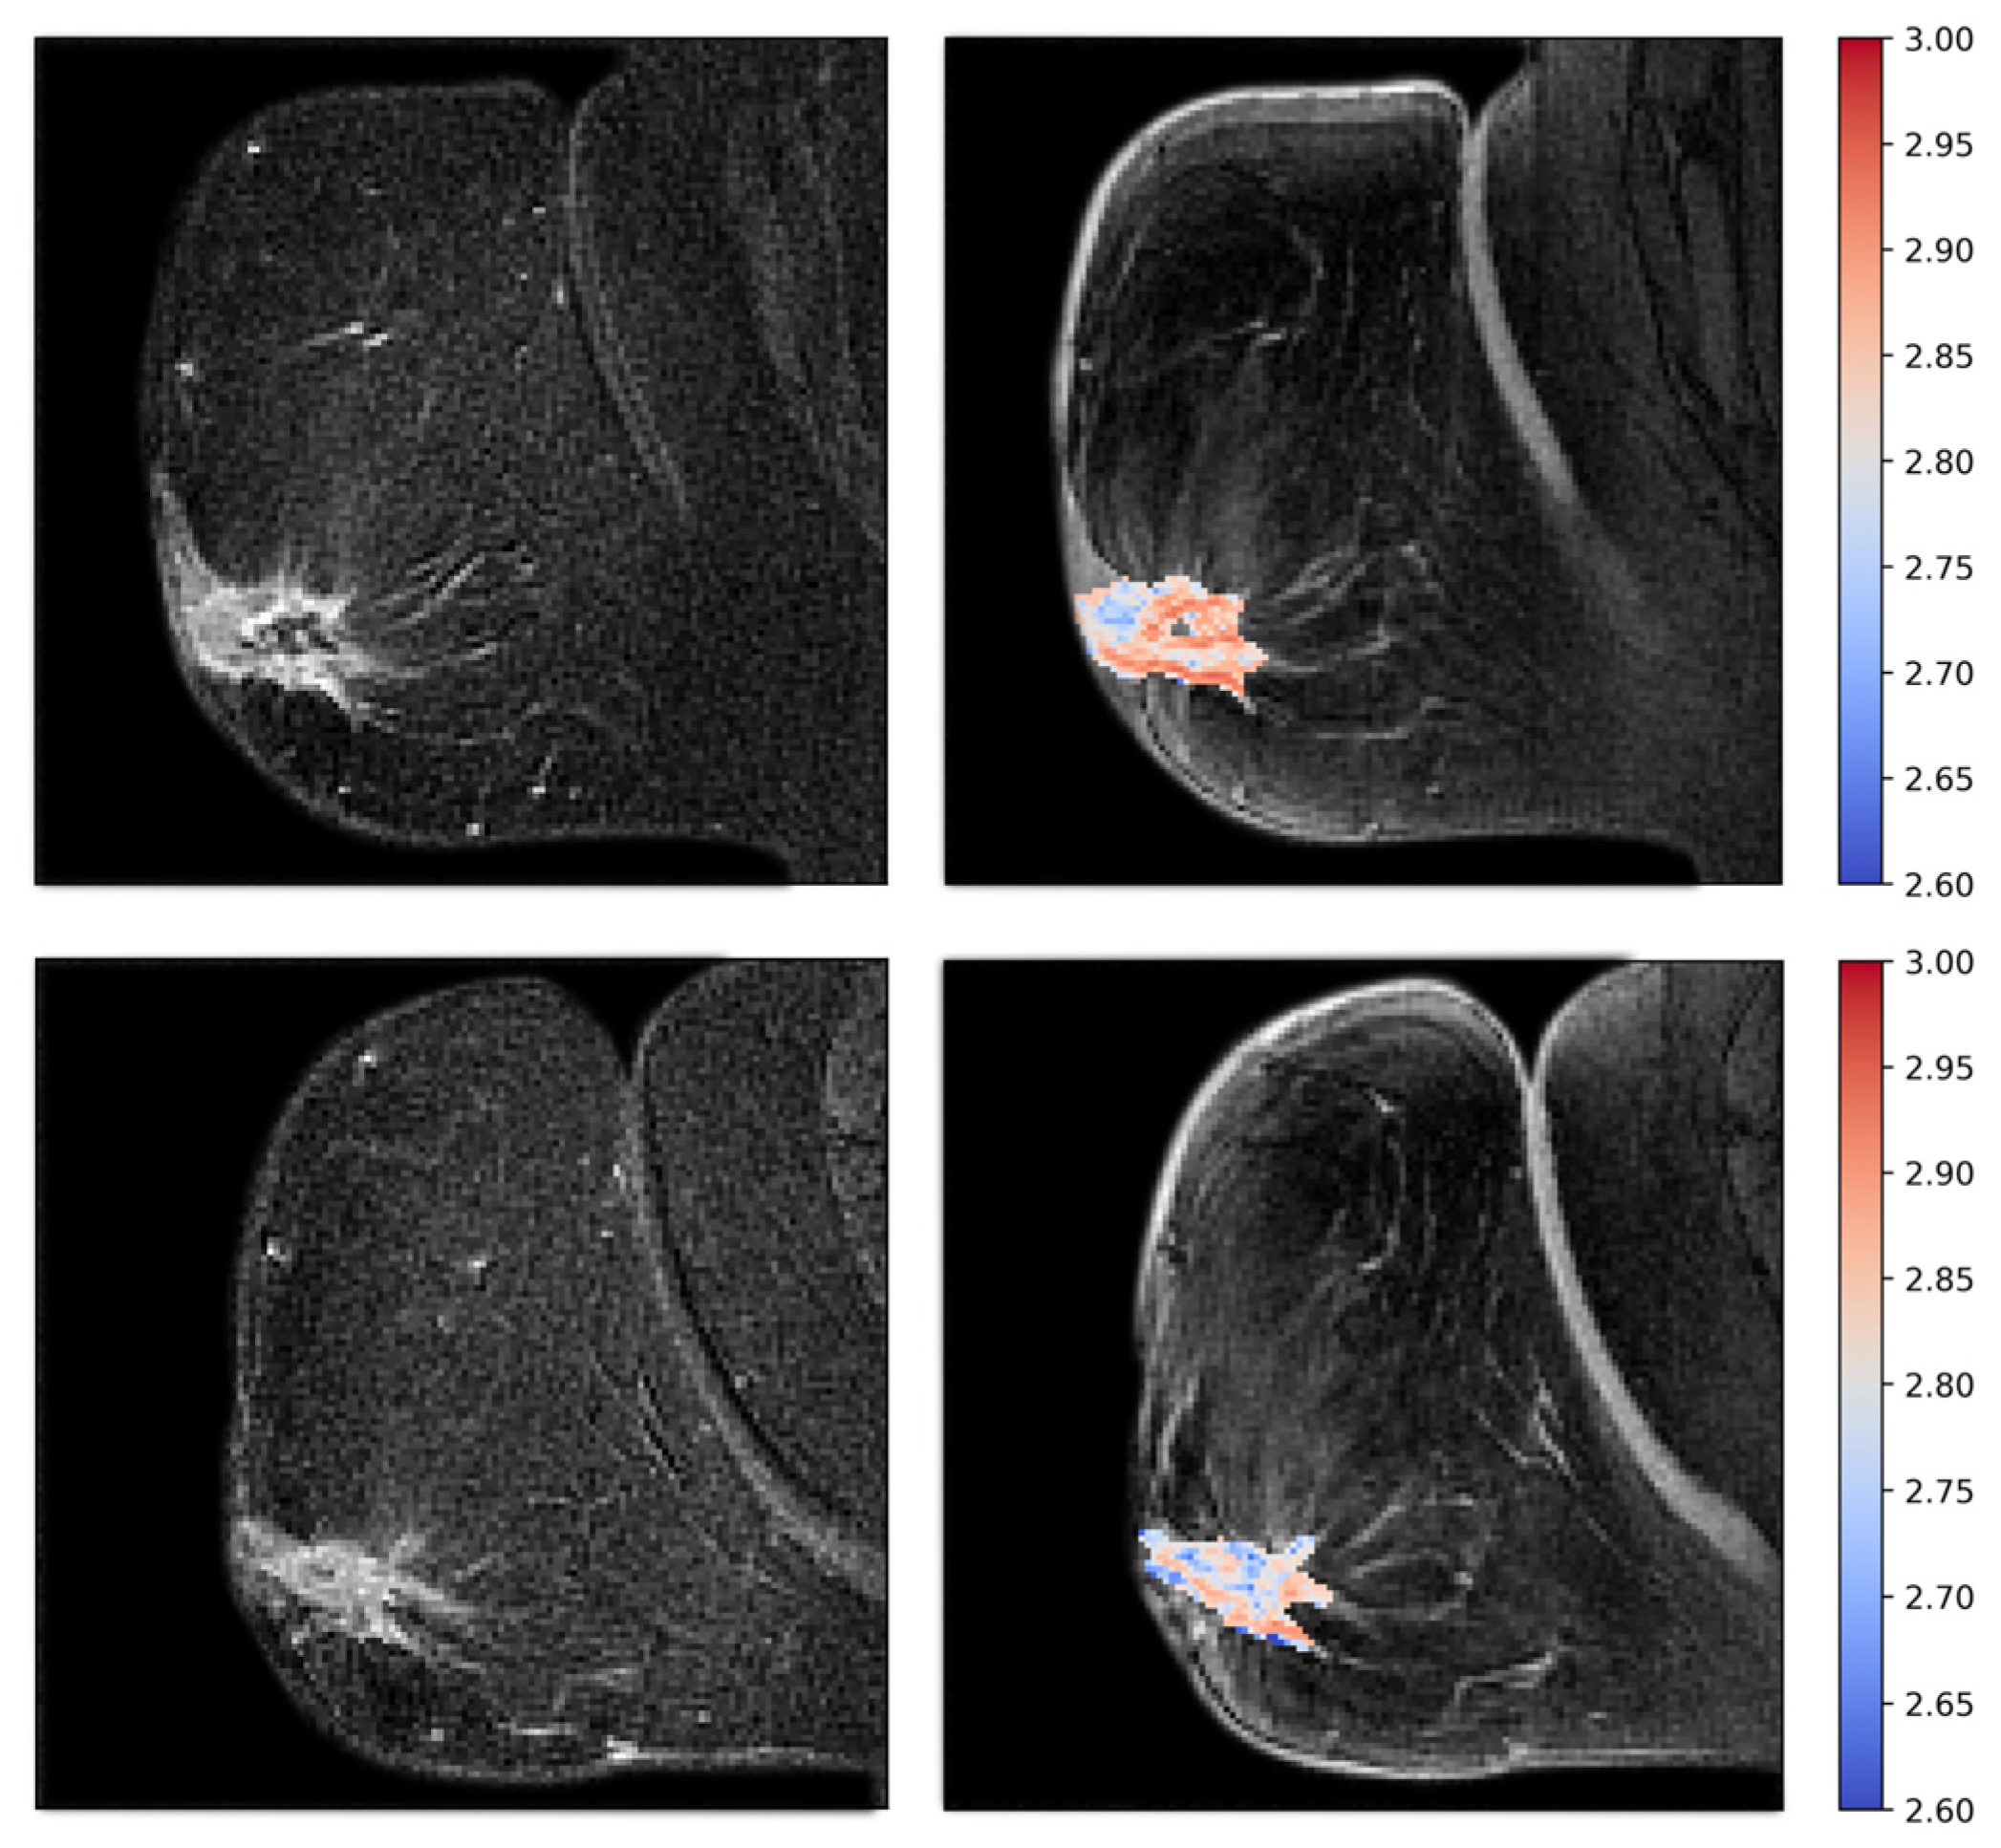

2.6. Tumor Vascular Architecture—Texture Analyses

3.3. Tumor Vascular Architecture